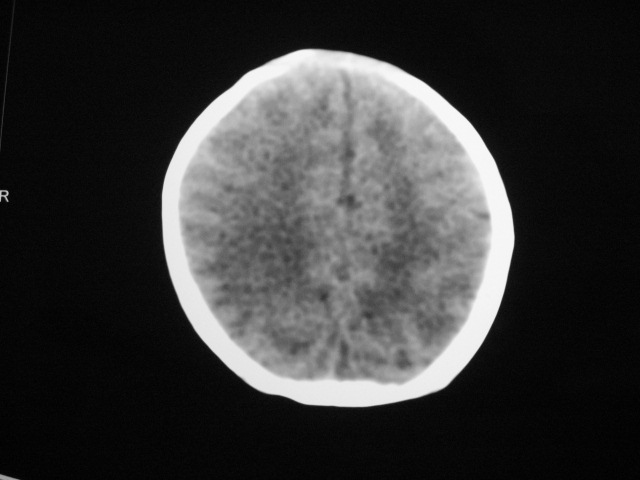

早产儿,1天,饮食呕吐,

双侧额叶见片状低密度灶,皮髓质分界模糊.患儿前囟略饱满,

患儿头颅ct示:皮质薄,髓质密度减低,脑回宽,脑沟浅,脑室系统无殊,中线结构居中,符合:早产儿颅脑ct改变。